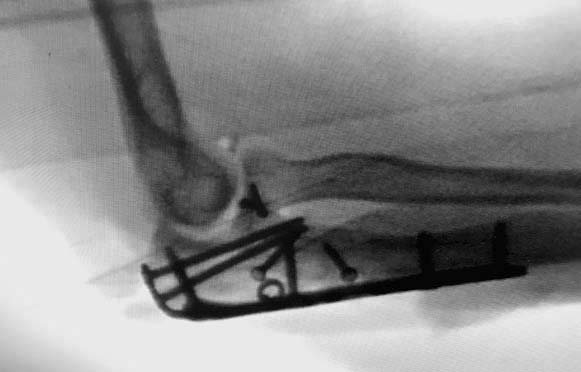

А так, здесь имеется многофрагментарный проксимальный перелом локтевого отростка с переломо-вывихом головки лучевой кости по классификации Mason III. Решение принимается на основании КТ срезов, потому что на боковом рентген снимке вроде отсутствует смещение, где сустав и контур Coronoid в одном блоке, а на прямом подозрение на смещение в Coronoid?

Для перелома локтевого отростка придуманы много пластин, надо выбрать по длине. А при краевых переломах головки ее окружность можно восстановить винтами 2 мм, но в данном случае имеется полный вывих головки и фиксация, даже специальной пластиной, может осложнится. Протез головки после удаления предупреждает нестабильность в суставе и деформацию оси конечности в будущем!

Конверсионные спицы на уровне проксимального отдела лучевой кости интересная идея, но на уровне перелома в области шейки трудно удержать головку. Предварительная репозиция локтевого отростка с временной установкой пластины, затем удаление экономит время. Доступ через локтевой отросток, где можно фиксировать или удалить головку с замещением, а потом установить пластину обратно на локтевой отросток!